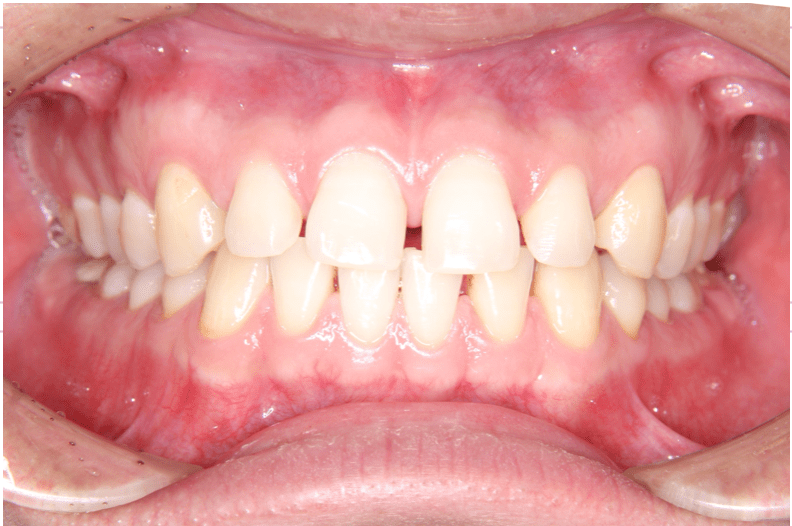

すきっ歯とは、文字通り隙間が空いている歯並びのことを指します。

治療前(右)

治療前(正面)

治療前(左)

歯列に隙間が見られます